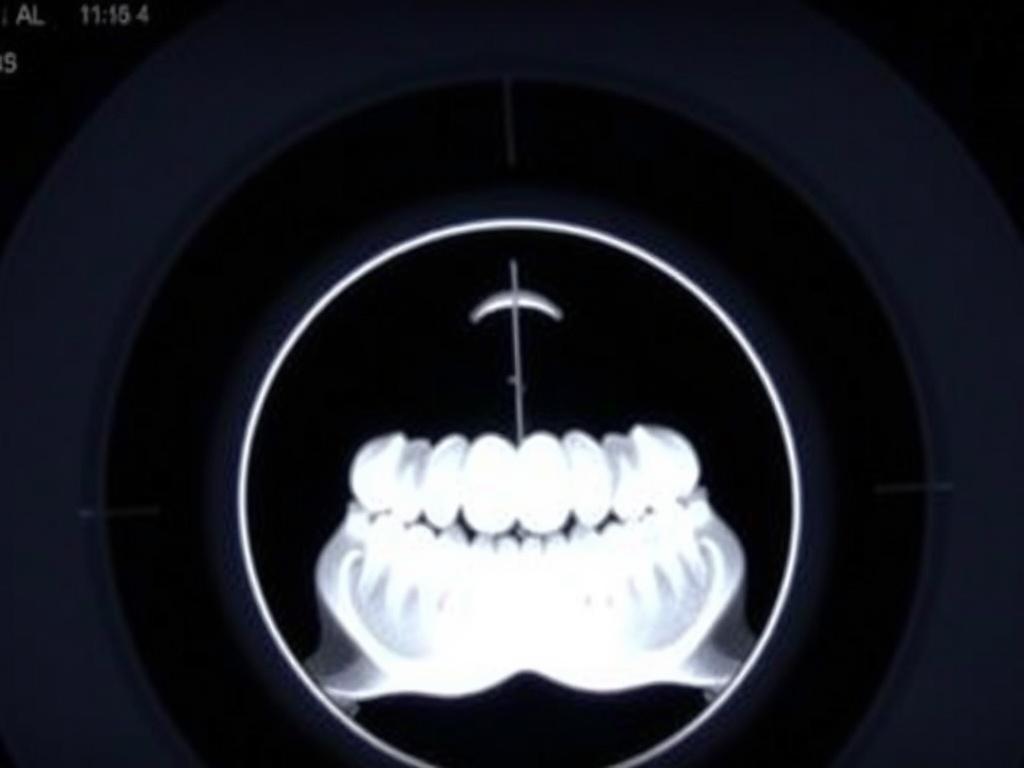

КТ зубов чаще всего называют конусно-лучевой компьютерной томографией, сокращённо КЛКТ. Это метод, который создаёт трёхмерное изображение зубов и челюстей: врач видит не одну плоскость, а серию «слоёв» — фронтальные, боковые, осевые и 3D‑модель. Благодаря этому можно подробно рассмотреть корни, костную ткань, соотношение зубов с нервами и пазухами.

Главное отличие от панорамного снимка — степень детализации. Панорамный рентген даёт общую картину, КТ показывает нюансы: кривизну корня, тонкие переломы, глубину кисты и толщину кости под имплантат. По сравнению с медицинской КТ головы, КЛКТ затрачивает меньше лучевой нагрузки и ориентирована именно на зубочелюстную область.

Отчёт по КТ включает снимки в трёх основных плоскостях и часто 3D‑рендер. Вот какие клинические вопросы решает врач с помощью этих данных.